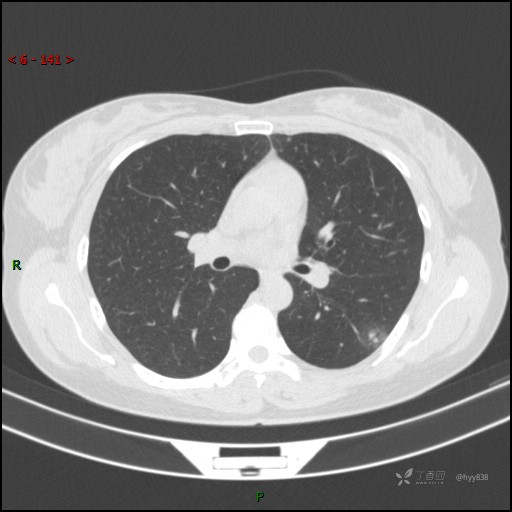

胸膜下“煎鸡蛋征”,感染 VS 炎症 VS 肿瘤,挑战有你---结果公布~

患者性别:女

患者年龄:46岁

简要病史:干咳半月伴左胸部不适

辅助检查:CT

临床诊断:结节

讨论:病变性质?